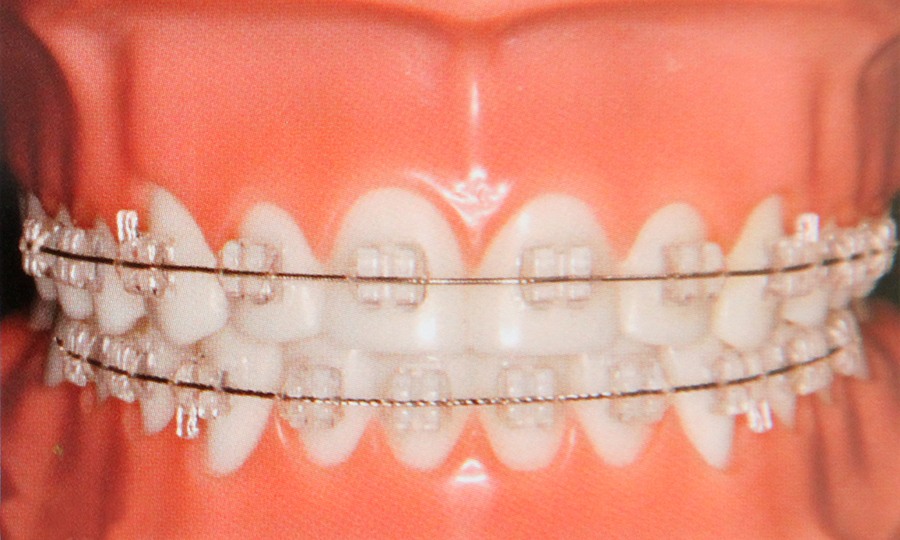

Aparatele fixe sunt alcatuite din bracheti aplicate pe fiecare dinte si o succesiune de arcuri ce asigura alinierea dintilor. Aceste bracheti pot fi metalici sau ceramici alternative pentru cei care nu vor ca aparatele sa fie vizibile.